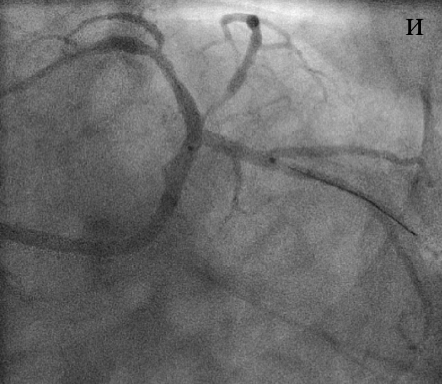

В устье ОВ с переходом на ее проксимальный сегмент был имплантирован стент XienceV (и), после чего выполнена постдилатация по методике «целующихся» баллонов (к). При контрольной КГ стентированные сегменты проходимы, достигнут хороший ангиографический результат (л).